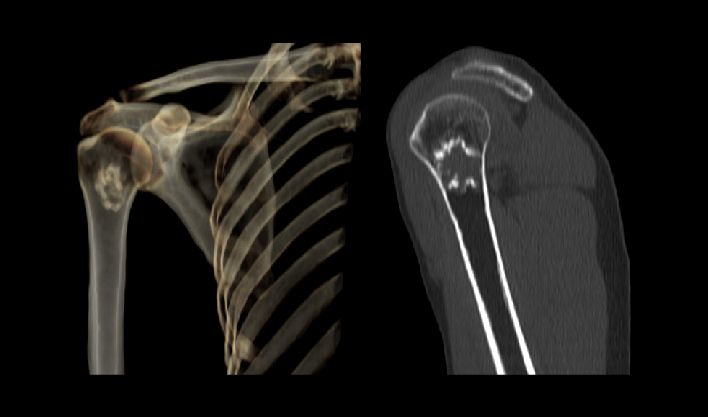

百万像素成像

1024x1024重建矩阵结合薄层成像,快速锁定微小病灶(如早期肿瘤、卒中病灶),助力急诊创伤、肿瘤筛查、卒中救治的“分秒必争"。

±30°机架倾斜

便于调整扫描角度,满足特殊疾病及体位扫描,提高诊断准确性,拓展设备应用范围。